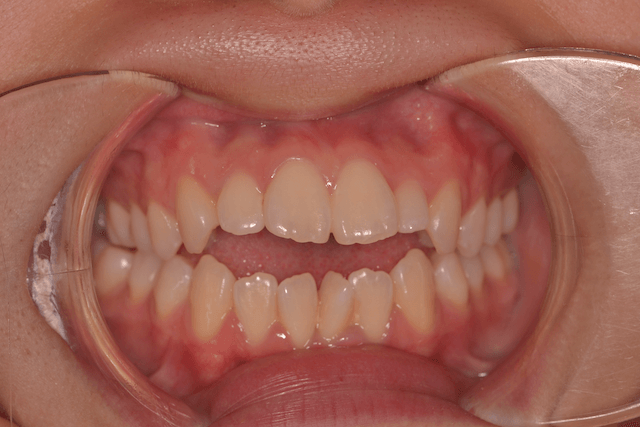

開咬(オープンバイト)を抜歯とDBSで改善した症例

※DBSとはダイレクトボンディングシステムと呼ばれており、ブラケットにワイヤーを通して歯を動かしていく矯正治療です。

患者情報

17歳女性

主訴

ガタガタの歯並びを直したい

行った治療内容

上下顎両側4番抜歯、DBS

治療のリスク

歯肉退縮、歯根吸収

治療期間

動的治療期間4年3か月 (来院がとびとびだった)

※ クリックして拡大することができます。